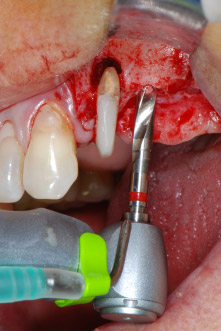

Въпреки това, ние се придържахме към първоначалния си план да запазим и двата зъба като абатмънти за временен мост по време на 6-месечната остеоинтеграция на имплантите. При повторна интервенция, ситуацията трябва да се преразгледа. Първо, в опит да се овладее ендо-перио проблема, останалата повърхност на зъба е внимателно обработена с пиезохирургично оборудване (Piezomed, W&H, използван с накрайник S1 под формата на шпатула, първоначално проектиран за ерозия на латералната синусна стена) (Фиг. 4).

След това апексът се изпилява със същия инструмент, за да се отстрани остатъчната инфектирана апикална тъкан и да се намали възможното допълнително усложнение по кореновите канали (апикоектомия) (Фиг. 5). Ретроградно запълване не е необходимо, защото ортоградното запълване току-що е ревизиран.